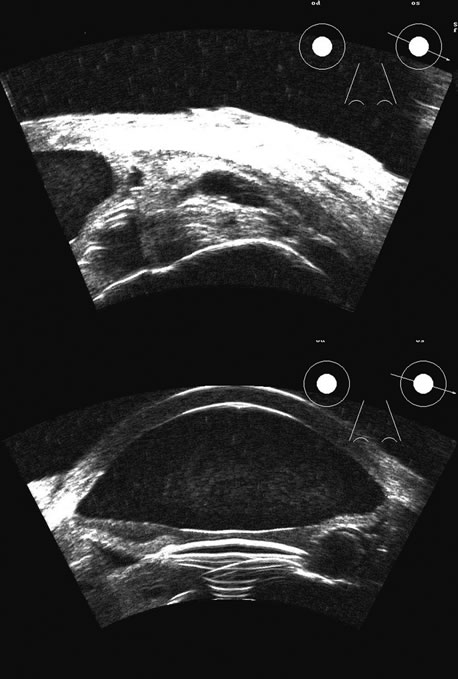

Malignant melanoma varies in its ultrasound presentation from a relatively homogeneous to heterogenous lesion on B-scan. The typical uveal melanoma absorbs sound so that the posterior section is relatively less echoic than the anterior aspect, producing a gradually decreasing amplitude, often to baseline on the A-scan (Fig. 21).

Fig. 21. An ocular tumor at the posterior pole showing the smooth convex border and solid internal reflectants typical of a melanoma.

Melanomas also have varying amounts of melanin, a highly acoustically reflective pigment. As noted, melanomas characteristically show high reflectivity anteriorly, with decreasing reflectance as the sound traverses the tissue. This produces the decreasing amplitude posteriorly in the tumor seen on A-scan and gray-scale B-scan. This effect often enhances the anterior scleral boundary. The posterior tumor border is thus measured as the first “rising” echo from the tumor decline, and it is most easily seen and accurately identified on B-scan.27

Metastatic carcinoma is more heterogeneous, producing a more uniform A-scan amplitude of roughly 50% to 80% of the “scleral” echo amplitude (see below) behind the tumor (Fig. 22). Hemangioma is a very highly reflective tumor with high amplitude all the way through the tumor of 80% to 100% of scleral echo amplitude (Fig. 23).

Fig. 22. Some hemangiomas and metastatic carcinomas may simulate a melanoma. They are differentiated on the basis of a very high amplitude internal echo complex for the hemangioma, a moderately low but sustained echo pattern for the metastasis, and an A-scan with decreasing reflectance as the tumor thickness is traversed. In the center scan of a melanoma, note the double anterior layer caused by edema fluid underlying the crest of the melanoma (arrow).

Fig. 23. A hemangioma of the posterior pole is usually very echoic, appearing solid on B-scan with little or no reduction in amplitude on A-scan between the retinal surface and the posterior tumor wall.